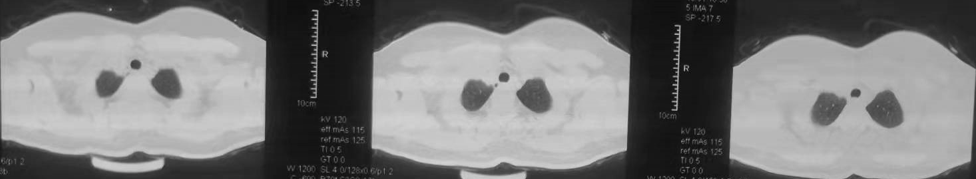

图1 颈胸部CT(2021-10-18):“1组淋巴结”增大(箭头所指)